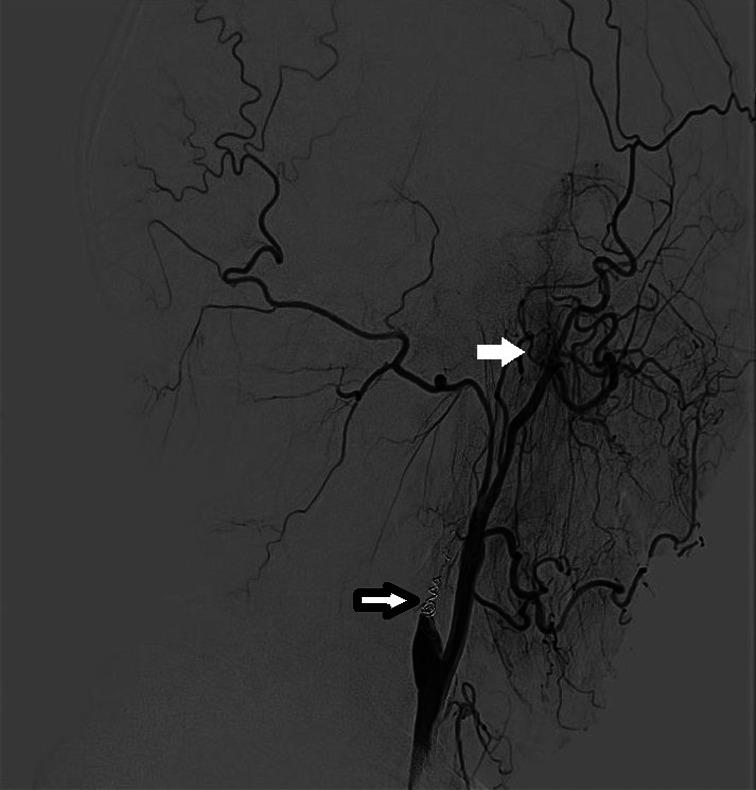

A 42-year-old man had a history of recurrent NPC that was treated with 2 cycles of chemoradiotherapies from 2017 to 2019. Five months after the second round of chemoradiotherapy, an episode of massive nasal bleeding occurred. As positron emission tomography (PET) scan revealed tumor recurrence in the left wall of nasopharynx, superselective embolization and subsequent intra-arterial infusion (IA, 4 times of cisplatin 60 mg + fluorouracil 1.0 g) were performed to stop bleeding and achieve tumor control. To date, the disease-free survival time has been over 1 year. No tumor recurrence or rebleeding is found except for alopecia on the left side.